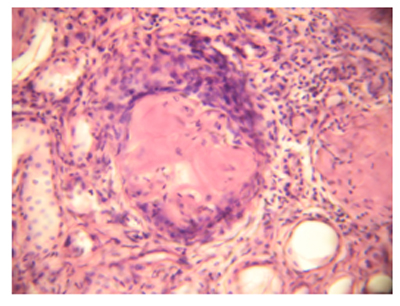

ՊՀ պայմանավորված լյարդի ախտահարումը դրսևորվել է ամիլոիդի առկայությամբ լյարդի դրունքային ուղիներում` անոթների, հատկապես զարկերակների և զարկերակիկների պատերում (նկ. 2): Ներբլթակային հենքում ամիլոիդոզն արտահայտված չէր:

Նկ. 2. Ամիլոիդային կուտակումներ լյարդի դրունքային զարկերակի պատում,հեմատոքսիլին- էոզին, x400 |